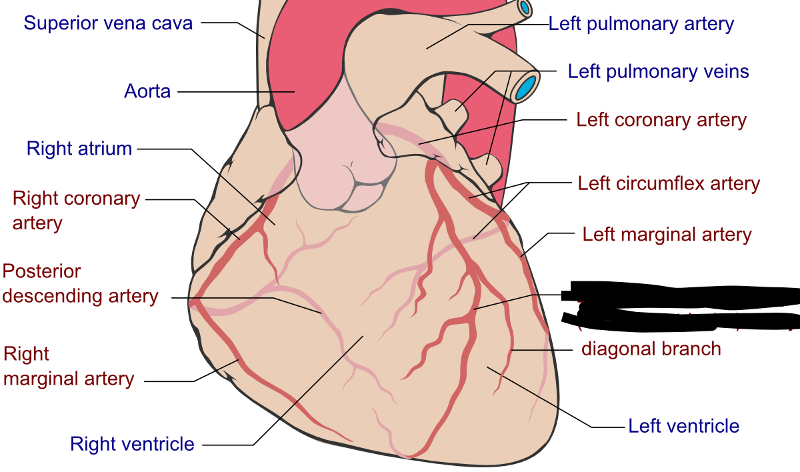

Circumflex branch (of the left coronary artery)

interventricular branch of the left coronary artery. = left anterior descending artery (LADA))

Left/right coronary artery

left/right pulmonary artery/vein

left/right ventricle